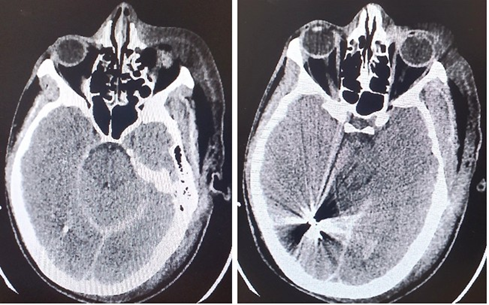

During the neurosurgical procedure, the following stages were performed: Left craniectomy, meningeal section and opening. A small puncture of the anterior part of the sagittal is found where the bleeding is successfully stopped. Wound closure in layers. He was taken under full sedation to the Intensive Care Unit (Figures 1-4, a and b).

Figure 1(a and b): CT Brain scan 24 hours (1st day) after the brain injury and the neurosurgery.